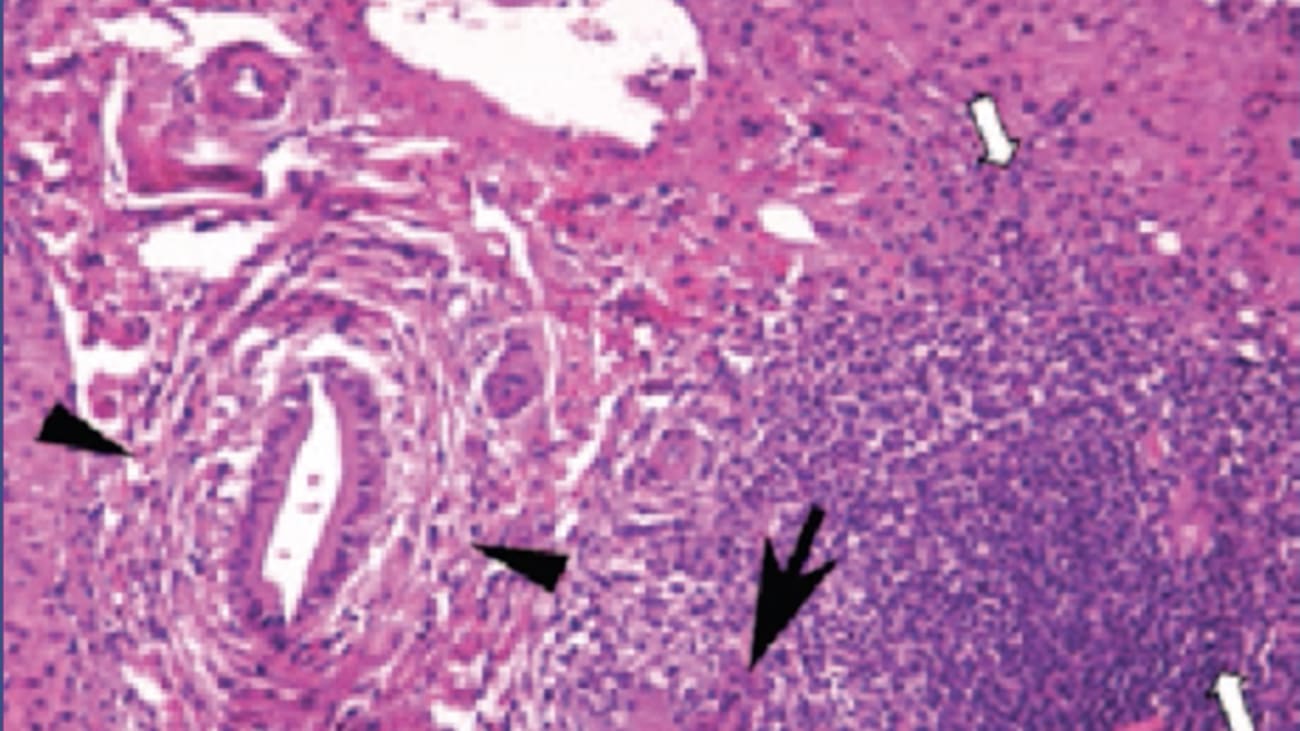

I'm joseph Oden. This lecture will focus on auto immune and metabolic liver disease. I'll be using a case based approach to illustrate key points for these diseases. The first case involves a 29 year old man who was noted to have abnormal LFTs after attempting to donate blood. He has no history of joined us or liver diseases. He has no history of alcohol abuse, intravenous drug use, tattoos nor any new medications supplements or herbal product use in the past six months. He works full time as a police officer and his family history is significant for hypertension and heart disease. On review of systems he complained only a fatigue and irritability over the past two months on exam he was thin had an IQ Terex Clara and the rest of the exam was basically normal without any evidence of chronic liver disease. He was noted to have a resting tremor. He has mild normal civic anemia and a platelet count of 110,000 L. T. And S. T. R. S. 1662 and 2198 respectively. The elk fasts was in the low side. About 58. Total Billy Rubin and direct Billy Rubin were 2.1 and 0.7 respectively and the cholesterol and triglyceride levels were normal. To further work up this gentleman's abnormal LFTs. An abdominal ultrasound was done which showed a mildly shrunken liver no state, Asus no gall stones and no biliary abnormalities and the spleen was unremarkable. Additionally the chest X ray and E. K. G are both un remarkable. The hepatitis A antibiotic level was negative. Hepatitis B. Service antibiotic level was positive. His surface androgen was negative. Hepatitis C. Antibody was also negative. The auto antibody tigers showed an A. An A. 1 to 40 anti smooth muscle antibody of 1 to 40 and the I. G. Level was only slightly above normal. The serum iron profile showed an iron level of 145 with a transparent saturation of 44% and the fertile level was high at 455. The surreal A plasma level was low at 12 and the LFO one anti trips in phenotype was MZ. So that's a lot of information to digest. But the first question obviously is what diagnostic test would be most useful in this case to confirm your suspected diagnosis. First choice is anti liver kidney Microsoft. Will antibody testing. Second choices, 80 p. seven b. genotyping question C. Is urinary copper tests. Question answer. D. Is hft genotyping and answer E. Z. Alpha one anti trips in Syrian serum enzyme activity level. I'll give you a few seconds to ponder your possible choices before discussing what would be the best answer. Okay. Mhm. For this question, the best answer would be C. Urinary copper tests, irritability. The Palestinian. The injury analysis low surreal A. Plasm and low Auckland facilities levels are all consistent with wilson disease. A genetic disorder of copper metabolism with elevated urinary copper secretion answer A. Could be considered anti L. Km antibody testing since autoimmune hepatitis is part of the differential in this case. Our anti L KM only rules out Type two autoimmune hepatitis, which is rare and more common in women, Children, and Europeans. APATPS seven B genotyping is really only useful in Wilson disease. When there's a relative with a known mutation, it's a very large jean with lots of possible mutations. HIV genotyping, it's not useful in this case. The patient did have an elevated ferreting level, but that by itself does not suggest to hereditary hemochromatosis and for 10 is an acute phase protein as you know, that can be elevated in many conditions. AlFA one anti trips and serum enzyme activity levels are not really predictive of liver disease. The ALPHA one anti trips and fema type is the better choice when you're trying to rule out liver disease from this deficiency. The MZ hetero zygote phenotype does not typically cause liver disease. The three most common causes of metabolic liver disease and adults are hereditary hemochromatosis. Wilson disease and ALPHA one anti trips and efficiency. The respect of genes involved are HFEATP 70 and serpent a one and both men and women are affected hemochromatosis may have a later onset in women than men hemochromatosis results in total body iron overload, which primarily affects the liver heart, pancreas, pituitary, thyroid skin and testes wilson disease or WD is characterized by inappropriate copper metabolism with deposition in the liver and brain with neuropsychiatric symptoms. Wilson disease and all for one anti trips in deficiency may present in childhood and may present with acute liver failure enough for one anti trips and efficiency. The lungs are affected due to decrease to parasites secretion of alpha one anti trips in And the liver is affected by accumulation of mutant alpha one anti trips in within the parasites. Thus Hamas, Vegas no mutations and serpent A one because only emphysema and do not affect the liver. Wilson's disease should always be considered in a patient under 40 years of age who presents with unexplained liver neurological or neurosurgical theatric disease, That's clinical spectrum ranges from asymptomatic academy glee or minor liver enzyme derangement to something as severe as fulminate liver failure with neuropsychiatric symptoms. Uh, Wilson's disease is often misdiagnosed as autoimmune, hepatitis uncle and fastest levels may be relatively low in Wilson disease. The presence of lows rule and plasm levels increase urine copper excretion and Kaiser fleischer rings help in the diagnosis of Wilson disease. If clinical and biochemical tests are inconclusive. Then confirmation can be done by quantification of copper in the liver. Every a liver biopsy or by molecular techniques like capital type or mutation analysis. Often on a board exam, you might be presented with a picture of somebody with Kaiser fleischer rings. The presence of Kayser fleischer rings is indicative of neurologic involvement but may not be present in all cases of a paddock involvement For hereditary hemochromatosis, the prevalence of Hamas, atticus mutations in the c. Y position is 1, 270 and two thirds will have elevated ferreting levels, but only 10% will actually have clinically significant. Iron overload The H 63 d. Hamas it gets rarely have iron overload screening the entire population for hereditary hemochromatosis is not recommended, but first degree relatives of hereditary hemochromatosis. Pro bands should be screened. The onset of iron overload in hereditary hemochromatosis is later in menstruating women than men in hereditary hemochromatosis. The affected organs include the heart, liver pancreas, skin, pituitary thyroid joints and testes as mentioned before. Iron overload may be present in a patient with an elevated for written and a normal transparent saturation, particularly in nine hft related iron overload or in a C. To 82 Y. H 63 D. Compound hetero saga. When making a diagnosis of hereditary hemochromatosis. Both transparent saturation and for certain levels should be obtained if either is abnormal Transparent saturation greater than 45% or 14 level above the upper limit of normal than HIV mutation analysis should be performed liver biopsy is recommended to stage the degree of liver disease in C. 2 82. Why Hamas. Egas or compound hetero hetero cigarettes. If trans emanates these are elevated or if the Sheraton level is greater than 1000 pearls prussian blue staining and measurement of a paddock iron content are helpful, especially in non Hft iron overload. If a spirit in serum ferreting level is less than 1000. Then in the liver biopsy probably is not needed. Since there's unlikely to be cirrhosis present. Empathic iron content determined by liver biopsy does correlate well with those estimated by MRI some of the classic findings in hereditary hemochromatosis. Our bronze skin as shown in the figure on the left muscle and histology. The pearls prussian blue stain can be used to show iron Granules within the parasites in secondary hemochromatosis. The iron standing is typically found in cup for cells and not in the parasites for one and two trips and efficiency should be suspected in any person who presents with unexplained liver or respiratory symptoms in Children liver disease associated with ALPHA one anti trips and efficiency presents with new NATO Cali static jaundice, abnormal LFTs, hepatitis or even cirrhosis. Adults typically present in the third or fourth decade of life with chronic hepatitis, cirrhosis or liver cancer. Non specific increases in billy Rubin, S. T and LT are observed. The gold standard for diagnosis is ALPHA one anti trips and phenotype determination by serum protein, ice electric focusing only one in five individuals. Hamas, IKEA's for the Z leo will develop liver disease. The mm phenotype is normal as mentioned before. Uh measurement of serum alpha one anti trips and activity is not diagnosis. Sorry, it's not diagnostic since alpha 1 80 is an acute phase protein. A liver biopsy. Make sure the presence of periodic acid Schiff positive. Global's the photo here shows a periodic acid Schiff stain. The parasite inclusions are made of MS faulted α one Anti trips and proteins those homes I guess for no if you want to into trips and mutations will not have inclusions nor will they have liver disease. These are the patients that have purely lung disease. Lastly, autoimmune hepatitis is an uncommon form of hepatitis that typically presents in younger women and is characterized by fatigue as well as elevated trans AM in aces G levels and A. And A. And alpha smooth muscle tigers A. And S. M. A. R. Not specific for autoimmune hepatitis and can commonly be seen in many other liver diseases as well as non liver conditions. Anti soluble liver antigen auto antibodies are directed against Tr nays these less common auto antibodies are highly disease specific for severe forms of Type one autoimmune hepatitis, Type two autoimmune hepatitis with anti L. Km antibiotic positivity is seen more often in Children women, Europeans and in autoimmune polly endocrine apathy. Candidacies active dermal dystrophy or A P. E. C. E. D. The cause of autoimmune hepatitis that is unknown but unlikely involves but likely involves exposure to a triggering agent example would be how fame in genetically susceptible individuals. The presentation of autoimmune hepatitis is highly variable. Many patients present with non specific symptoms such as fatigue along with elevated S. T. And LT levels. However, 10% of patients present with symptoms of acute liver failure and 10-20% will present with cirrhosis. 80% of affected individuals are female and all races are represented. 50% of autoimmune hepatitis patients do have some other autoimmune disease as well, such as autoimmune thyroid disease or rheumatoid arthritis like viral hepatitis, the A. S. T. And A. T. L. T levels may be in the thousands. Liver biopsy collects classically shows interface hepatitis with sheets of plasma cells and lobular necro inflammatory activity. A validated scoring system by the international Auto Immune Hepatology group is available for diagnosis of questionable cases but most territories treatment if uncertain. This slide shows the scoring system that's been developed that includes both clinical features as well as laboratory data and histology as well. And at the bottom you'll see that also responds to treatment is also a factor used in the diagnosis of ordering hepatitis since most patients do respond to steroid treatment. Okay, let's turn our attention towards treatment modalities in the case that we presented earlier, the suspected diagnosis was confirmed. What treatment should be initiated next A is ALPHA one antitrust enzyme replacement therapy. B zinc therapy. See predniSONE therapy. D. penicillin. Mean therapy and E therapeutic for lobotomy. The best answer to this question would be D. penicillin. Mean therapy which is useful in symptomatic wilson disease and acts by calculating serum copper A. is a obvious treatment for Alpha one anti trips and disease. The zinc therapy is useful in asymptomatic wilson disease. By reducing copper uptake in the intestines. predniSONE therapy has not been shown to be useful in Wilson disease, but as useful in autoimmune hepatitis. As we mentioned, therapeutic for lobotomy effectively reduces subotic iron stores over time. But this is not an effective treatment in Wilson disease. Initiating Wilson disease treatment can be somewhat complex and in some cases can actually precipitate liver failure. So I would recommend referring the patient to a liver transplant center for initiation of treatment and then have the patient return for follow up maintenance treatment. A conservative treatment for patients can just be dietary modification and the use of antioxidants such as vitamin E. Medical treatment with key leaders, non coagulating agents and combination therapy can be useful. Most common treatment for symptomatic patients as mentioned before as penicillin mean, and it should be done with a low dose initially and slowly titrate up to a higher dose uh supplemental paradox scene is necessary when treating somebody with penicillin. Mean, newer agent is trance scene which may be somewhat more effective than penicillin mean and can be used in those who are refractory to penicillin mean, but it is also considered the first line treatment for Wilson disease. The ammonium tetra thio Malibu is really preferred for those with predominantly neurological symptoms for those with a symptomatic disease and those requiring maintenance therapy. Zinc therapy is quite useful since it blocks copper absorption from the intestine. And you can check the efficacy of treatment by checking on urinary copper levels. A combination therapy can be used as an emergency treatment for those with copper overload informant liver failure, dialysis. Human filtration and plasmapheresis can be last ditch attempts to try and keep these patients from needing a liver transplant for hereditary hemochromatosis, therapeutic for lobotomy is the recommended treatment. One unit the blood contains approximately 200 to 250 mg of iron depending on the hemoglobin concentration and should be removed once or twice per week as tolerated initially until the Farrington level drops below 100 micrograms per liter. The frequency of maintenance flow, body fat, body ME is variable. You can use parental iron population in non HIV hemochromatosis and X rayed and orally administered iron key later has been approved for treatment of secondary iron overload due to ineffective Northrop oasis supplemental vitamin C should be avoided in iron loaded patients. Regression of cirrhosis is not observed with the Bottom ME, but other conditions related to human comatose. IsSE do improve The treatment of over 1 80 deficiency for those with liver involvement is somewhat different For those who just have lung involvement, smoking cessation may be helpful for both lung disease and liver disease as well as avoiding environmental and occupational pollutants as best you can for the lungs vaccination for influenza and pneumococcal pneumonia is beneficial for those with liver disease. Vaccination against hepatitis A and B. Is recommended for those with liver disease Required liver transplantation. The five year survival rate is over 90%. Mhm. Combination treatment with glucocorticoids plus is a thigh A print Is traditionally used for autoimmune hepatitis. Over 90% of patients respond to this treatment. TPM T activity should be checked prior to addition of as a thigh print. Trans am in is in I. G. Levels are used to guide therapy but may not correlate with the degree of hepatic inflammation seen by liver biopsy. The goal of therapy is to normalize trans emanates and big levels. Five per scan may be helpful in monitoring therapy response, especially in those with normal adult and S levels before withdrawing therapy. After two plus years of normal enzyme levels, A liver biopsy is recommended. 50% of patients unfortunately have a recurrence within five years. Recurrence is treated the same way as the initial episode. However, lifelong treatment with as a fire print or low dose pregnant zone or buddhist need is recommended. 20% of those who recur to progress to cirrhosis and the presence of anti act and positive antibiotics correlates with a poor prognosis and death. Let's see if we have time to go through a second case. A 42 year old african american, woman with a history of thyroid disease, develops fatigue over two months. Blood tests reveal abnormal LFTs. She has no significant alcohol or family history nor any new medications or HDs used in the past six months on exam. Her square are an esoteric. Her lungs are clear and a heart has a regular rhythm. Her abdominal exam is benign and she has no stigma of chronic liver disease. The cbc and platelet counter normal as well as the TSH 18 A str significantly elevated alkaline phosphate level is also somewhat elevated. Total bilirubin, indirect billy Rubin are mildly elevated as well. Uh huh. Hepatitis virus ideologies are negative except for a positive core antibody I. G. M. For hepatitis B. Her I. G level is high and her in a tighter is 123 20 with an anti smooth muscle antibiotic tighter up 1 80 mm. Her iron level is normal. Her transparent saturation is 35% or ferreting is 1200 and their survival a plasma in is normal at 25 her of a one anti trips and prototype is mm with normal serum activity. An ultrasound did not show any abnormalities. So what liver biopsy finding would support the lengthy diagnosis? A A floor duck lesion be granulomas in the liver C interface. Hepatitis with plasma cells. The positive copper staining E onion, skin fibrosis and by all dot loss. Okay, if you're thinking that this is a probable case of autoimmune hepatitis then C. Is the right answer interface. Hepatitis with plasma cells is a characteristic finding of autoimmune. Hepatitis Floor Duck lesion is typically seen in primary biliary cirrhosis or cholangitis. As we say. Now granulomas can be found in PBC sarcoidosis, crones or a number of other conditions positive copper staining would support a diagnosis of wilson disease that can also be seen in chronic hoist Asus under skin fibrosis and bob black gloss is characteristic of primary or secondary sclerosing cholangitis. This case does meet the criteria for probable on immune hepatitis using the simplified autoimmune hepatitis scoring system. If the histology turns out to be compatible, this would make it a definite autoimmune hepatitis case. Of course. In regular practice, most people do not rely on the scoring system. Here's a copy of the biopsy. You can see the arrow is pointing to the portal tracked as well as to the area with suggestions of interface hepatitis based on the liver biopsy. What additional tests might you order anti Okay, m antibodies I am a antibodies, anti smooth muscle antibodies, anti soluble liver androgen antibodies or P anCA antibodies. Uh actually there's two answers which would be correct here. One would be be anti mitochondrial antibodies because the floor duck lesion was shown on the biopsy and also there is under skin fibrosis shown in a second bile duct seen in the portal track, which is consistent with PSC and the atypical perry nuclear anti neutrophils. Cytoplasmic antibodies are consistent with PSC. This is not uncommon to see overlap between autoimmune liver diseases. Occasionally it's overlap between autoimmune hepatitis and PVC has suggested in this case or between autoimmune hepatitis and PSC. Over between PBC and PSC is rare. There is a difference between the sex ratios for autoimmune hepatitis and PBC versus PSC. With more of a male predominance in PSC. Than seen in autoimmune hepatitis or PBC in the age of diagnosis is somewhat different for the three diseases. The immune target is also different where don't even hepatitis is more a pad of cellular and PBC and PSC or more cola static. And this is reflected in the enzyme elevations Seen in the three different diseases in the auto antibodies predominantly seeing the three diseases are different. You can see And a positivity and all three diseases. And there are reports of up to maybe 5% of patients with autoimmune hepatitis having positive Emma. Mhm. So when you're trying to make a diagnosis of overlap, you really do have to rely on histology and not go just by antibiotics, ideologies or biochemical findings. Yeah. And you can see the white arrows show you an area of interface hepatitis. The large arrowhead shows you an area of a florida, duck lesion and the two smaller arrows identify an area with onion skin fibrosis typical of PSC. In this case the Obama did come back positive? The P. AnCA was negative and M. R. C. P. Was normal. What treatment regimen would you? A ploy in this case predniSONE and a supply print if your destination and he's a fire. Print. Our zodiacs, E. Coli predniSONE is a thigh print and or so. Dioxin call it Or there's a vaccine collate and six MP. So the best answer would be D. predniSONE is a tire print. Anderson taxi. Cool it Bds and I could be substituted for pregnant zone if desired. Destiny. It is useful in that it limits side effects that are seen with systemic glucocorticoids such as predniSONE or brightness alone. Happy Destiny should not be used in patients with cirrhosis. However, and studies have shown that it's best to add as a fire prin within four weeks of starting pregnant zone for autoimmune hepatitis. This patient's S and at all levels did not decrease on appropriate therapy. What would you do next? A checker, serum apple and anti trips in level B. Question her alcohol use C. Review treatment, compliance and use of herbal and dietary supplements. D repeated a liver biopsy. E initiate second line therapy for autoimmune hepatitis. The best answer is C review treatment compliance and use of herbal and dietary supplements. Many patients because of side effects will self stop steroid treatment. Also uneven hepatitis can be mimicked by urban dietary supplement news and some herbal and dietary supplements will actually induce an autoimmune Hepatitis C genotype in this case she confirmed compliance and denied any HDs use the business is necessitated starting her on alternative therapy. Mhm. One of the options and alternative therapy is to substitute micro family for Elizabeth. I print the only time that you would not want to substitute michael Fennell. It is if the patient was pregnant or intended to become pregnant in the near future. There aren't any other approved salvage therapies for patients with autoimmune hepatitis increasingly technology messes being used as a substitute for patients that don't respond to predniSONE is a thigh print. There have also been other smaller studies looking at cyclosporin, rapper masonry talks a map or even on flex a map for treatment of refractory or immune hepatitis. There are special populations that should be considered when treating patients with autoimmune hepatitis uh during pregnancy it's safe to continue using predniSONE as well as a this is a tire print uh d compensated cirrhosis and from liver failure to to order. And hepatitis is another special population to consider use of high dose immunosuppressive medications and these groups may actually increase the risk of life threatening infections and should be avoided in Children ordering hepatitis and PSC overlap is very common. All Children with the diagnosis of autoimmune hepatitis should be screened for PSC as well. After a liver transplant. You can have a recurrence of autoimmune hepatitis interestingly. You can also see this de novo autoimmune hepatitis or plasma cell hepatitis developing patients that were transplanted for other liver diseases as well. The treatment is actually very similar to treatment pre liver transplant using predniSONE as the mainstay of therapy. obviously one should do a liver biopsy to rule out rejection as the cause of the elevated liver numbers. There are specific dose recommendations for the treatment of autoimmune hepatitis. However, one can customize therapy based on the severity of the initial presentation. There are many potential pitfalls and common errors associated with the diagnosis of autoimmune hepatitis. Differentiating drug or toxin induced hepatitis from autoimmune hepatitis can be difficult, especially without a careful history. The new checkpoint inhibitors for cancer therapy induces steroid responsive hepatitis that does not have the characteristic histology and auto antibodies associated with autoimmune hepatitis, no positive area and then die smooth muscle antibiotics are closely associated with autoimmune hepatitis. They can also frequently be seen in other liver diseases, including non alcoholic fatty liver disease. Given how common non alcoholic fatty liver disease is. It's not surprising that you do see overlap cases between natural tea and autoimmune hepatitis and those diagnosed with PBC or PBC, a diagnosis of autoimmune hepatitis requires histological changes. He noted on liver biopsy along with the characteristics neurological abnormalities. Also in most cases the L. T. S. T levels should be at least five times the upper limit of normal. Lastly, in those presenting with cirrhosis, the diagnosis of autoimmune hepatitis may be missed because of absent hepatic inflammation on the liver biopsy is known as burnt out autoimmune hepatitis. Okay, this is the final slide here are some take home points. There aren't likely to be more than two cases of autoimmune hepatitis on a board exam. If a second autoimmune hepatitis case pops up, it's probably an overlap case with PBC or PSC. Or perhaps drug induced autoimmune liver disease or post transplant plasma cell hepatitis. And remember that in a positivity and elevated IgG levels are very non specific. No more than one case of hereditary hemochromatosis. Wilson's disease or alpha one Anti trips and deficiency are likely to show up on any exam. Typically, they'll show the characteristic histology for one of these diseases. For a liver disease case with neurological symptoms. Consider not only Wilson disease but also poor furious or familial amyloidosis. Piling neuropathy, which are less common genetic metabolic diseases that can also be occurred by the liver transplantation. Okay, that's a lot of information. Here's an additional question. Just to see who was paying attention for which therapy should supplemental vitamin B6B given A level one anti trips and enzyme replacement therapy. B zinc therapy, See predniSONE therapy, D. penicillin. Mean, therapy for e therapeutics, lobotomy. The correct answer for this question is deep penicillin therapy. penicillin. Mean binds both copper and vitamin B6, which increases their urinary excretion. Therefore, Vitamin B6 replacement therapy is required when given penicillin. Mean